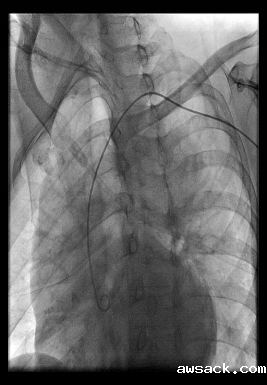

IABP(主动脉内球囊反搏):可降低主动脉阻抗,增加主动脉舒张压,而降低心肌耗氧,增加氧供,达到改善心功能的目的。